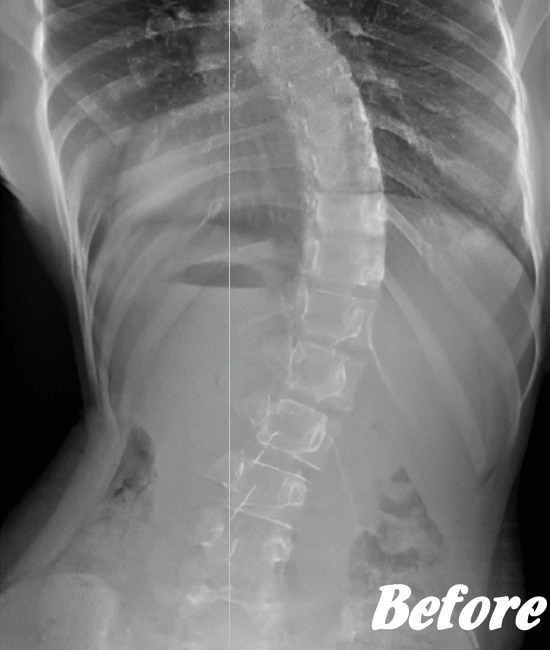

病院では、側弯の程度はレントゲンによる画像検査で弯曲の程度を調べます。

Cobb角(コブ角)とは、背骨の曲がり具合の角度を表す用語ですが、コブ角が10~25度程度なら経過観察。コブ角が25°~40°程度ならコルセットなどの装具を装着する療法、コブ角が40°~50°以上であれば手術…といった目安になります。

軽度の突発性側弯症であれば、運動療法で経過観察、進行性であれば専用のコルセットなどの装具着用。悪化する場合は、外科的手術で器具を埋め込み脊柱を固定することが検討されます。

先天性や弯曲角度が大きい突発性側弯症は適応外になりますが、普段の姿勢の悪さに起因する機能性側弯症や初~中期の突発性側弯症であれば、施術対象になります。

ただし、弯曲が20°以上になると改善が難しくなってきます。また、脊柱(背骨)が側屈しているだけなら良いのですが、椎骨が回旋してしまっている場合の改善は、肋骨の変形もともなうため改善が難しくなります。

したがって、側弯症は腰周りの筋肉を緩め腰の骨をまっすぐにしていくことを中心に、施術を行っていきます。腰がまっすぐになれば、身体はバランスを保とうと勝手に上部もまっすぐにしてくれます。